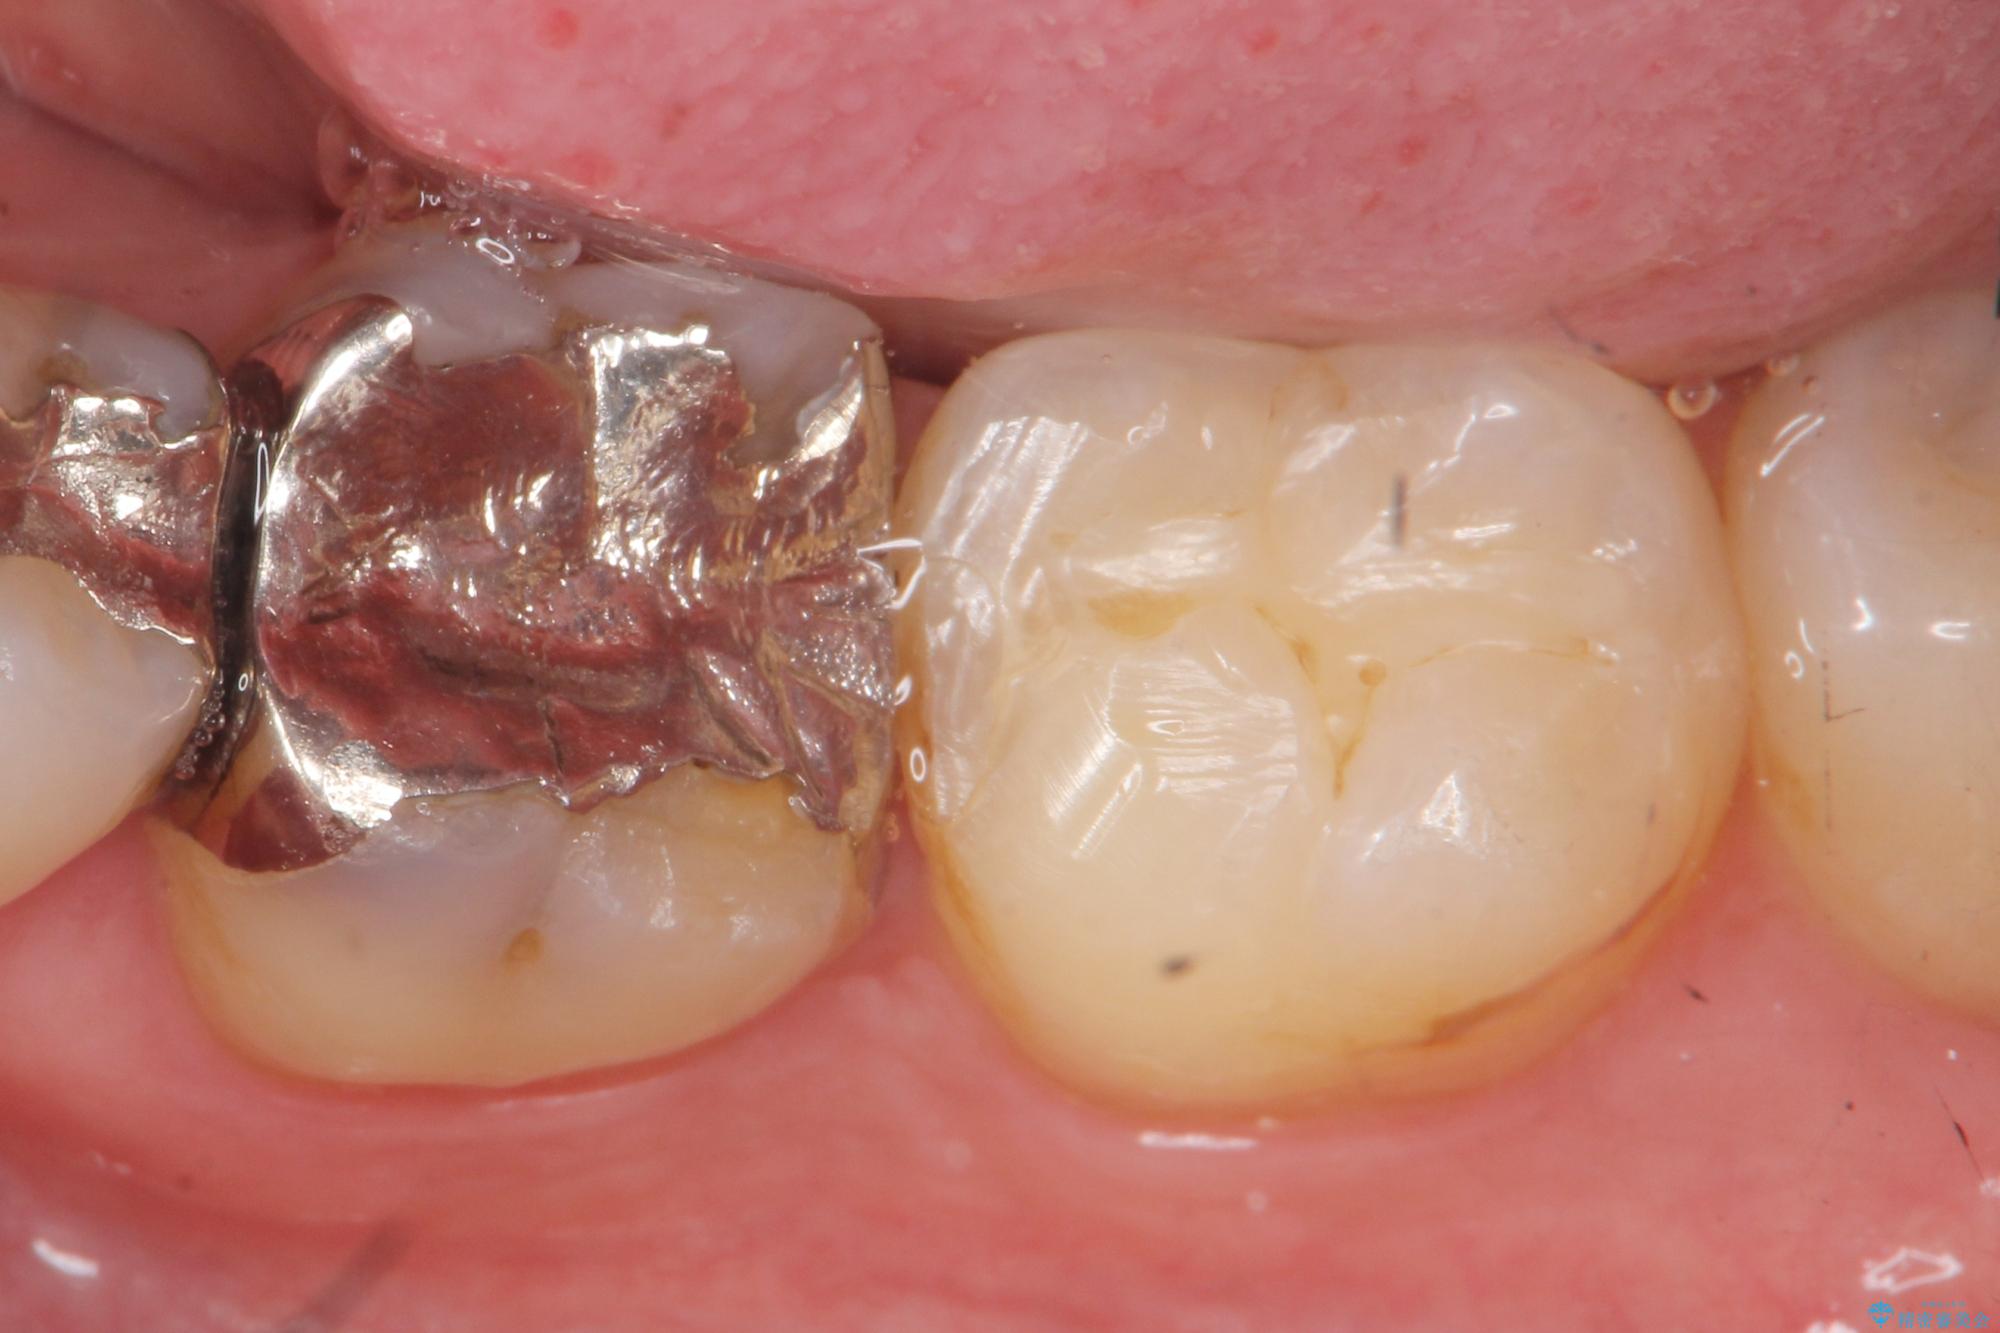

食べ物がよく詰まる、見た目も悪いので銀歯をやり替えたいとご来院された患者様です。

治療計画

銀歯の適合や形態不良により、食べ物が非常に挟まりやすく、虫歯の再発も銀歯の下に認められる状態でした。

不適合な修復物、虫歯の除去を丁寧におこなったのち、清掃しやすい形態へと回復する精密なセラミック治療を行います。